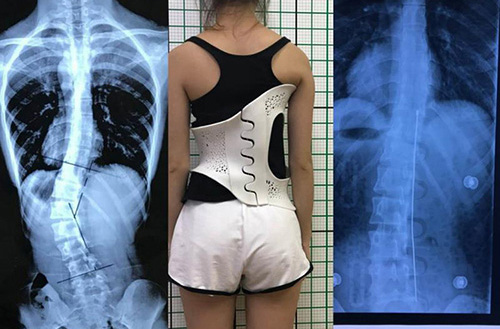

此外,在外固定支具研制方面,3D打印所起到的作用也不容忽視。對于意外摔傷導致骨折的患者來說,適宜的熱塑夾板、可卸式泡沫夾板、高分子夾板等外固定支具,有助于幫助患者快速恢復,并降低發生二次骨折的風險。

(3D掃描和3D打印技術輔助制造的個性化脊柱矯正支具)